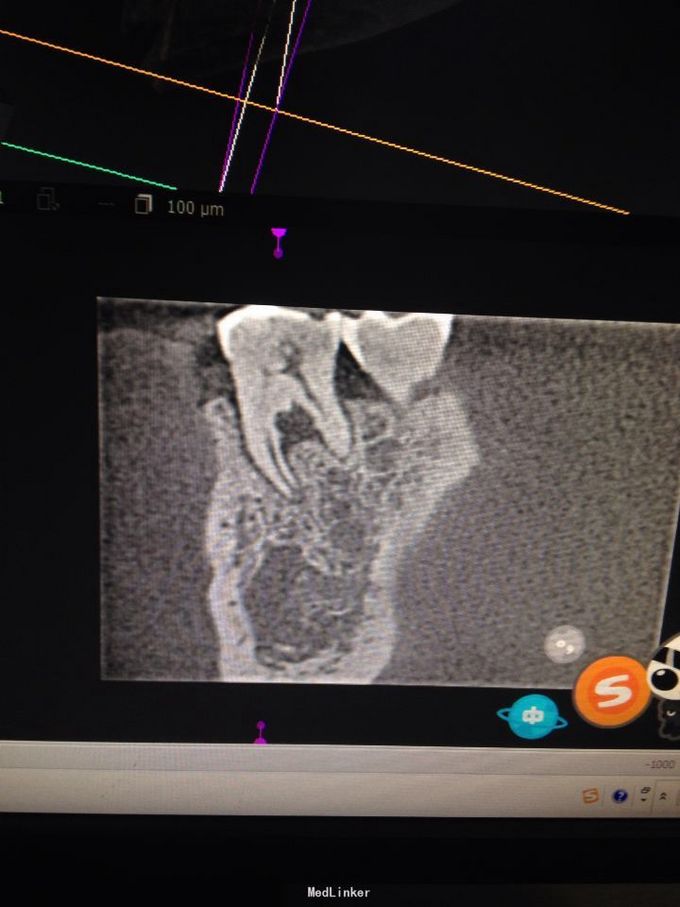

牙根纵折

慢性根尖周炎 慢性根尖周炎 根尖周炎

牙龈肿痛伴咬合疼一月余。一月前,突然发生右下牙齿疼痛,呈持续性,阵发性。期间自服消炎药,疼痛减轻。近这两周,再次疼痛,伴咬合疼,遂来诊。

右下六颊侧见窦道,积压见脓液溢出,扪疼明显,扣疼剧烈。牙冠完整,未见龋坏发生。

询问病史有咬硬物硌牙史。诊断:牙根纵折,慢性根尖周炎急性发作。 局麻下微创拔除。